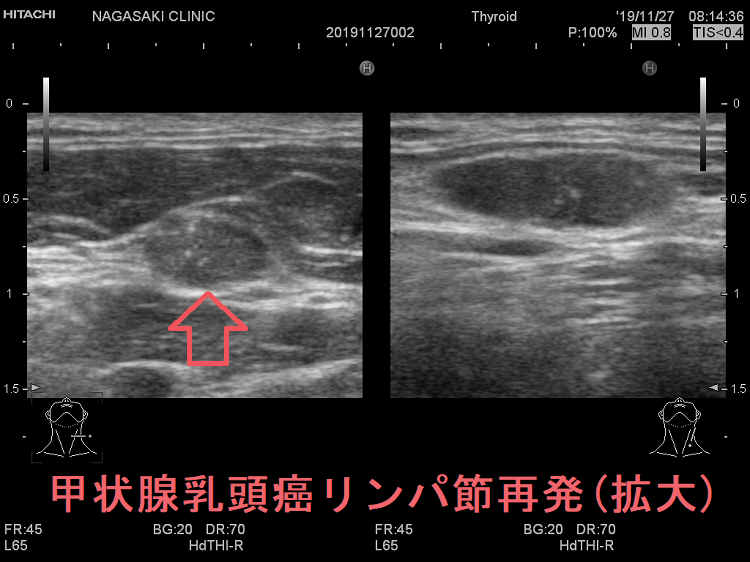

甲状腺乳頭癌リンパ節再発 超音波エコー画像

甲状腺乳頭癌のリンパ節再発 超音波エコー画像;リンパ門は消失し、砂粒状石灰化が著明

甲状腺乳頭癌のリンパ節再発(拡大) 超音波エコー画像

甲状腺乳頭癌のリンパ節再発(拡大) 超音波エコー画像;リンパ門は消失し、砂粒状石灰化が著明